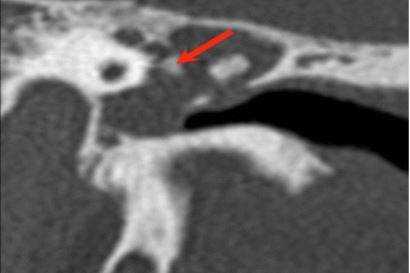

У одного пациента на КТ определялись двусторонняя аномалия внутреннего уха по типу Мондини (рис. 3), двусторонний локальный порок развития цепи слуховых косточек, костная облитерация лабиринта, включая улитку справа. На МРТ внутриулитковая жидкость справа не определялась, слева количество внутриулитковой жидкости было в норме.

Рис. 3. КТ, аксиальная проекция. Аномалия Мондини, состояние после КИ.